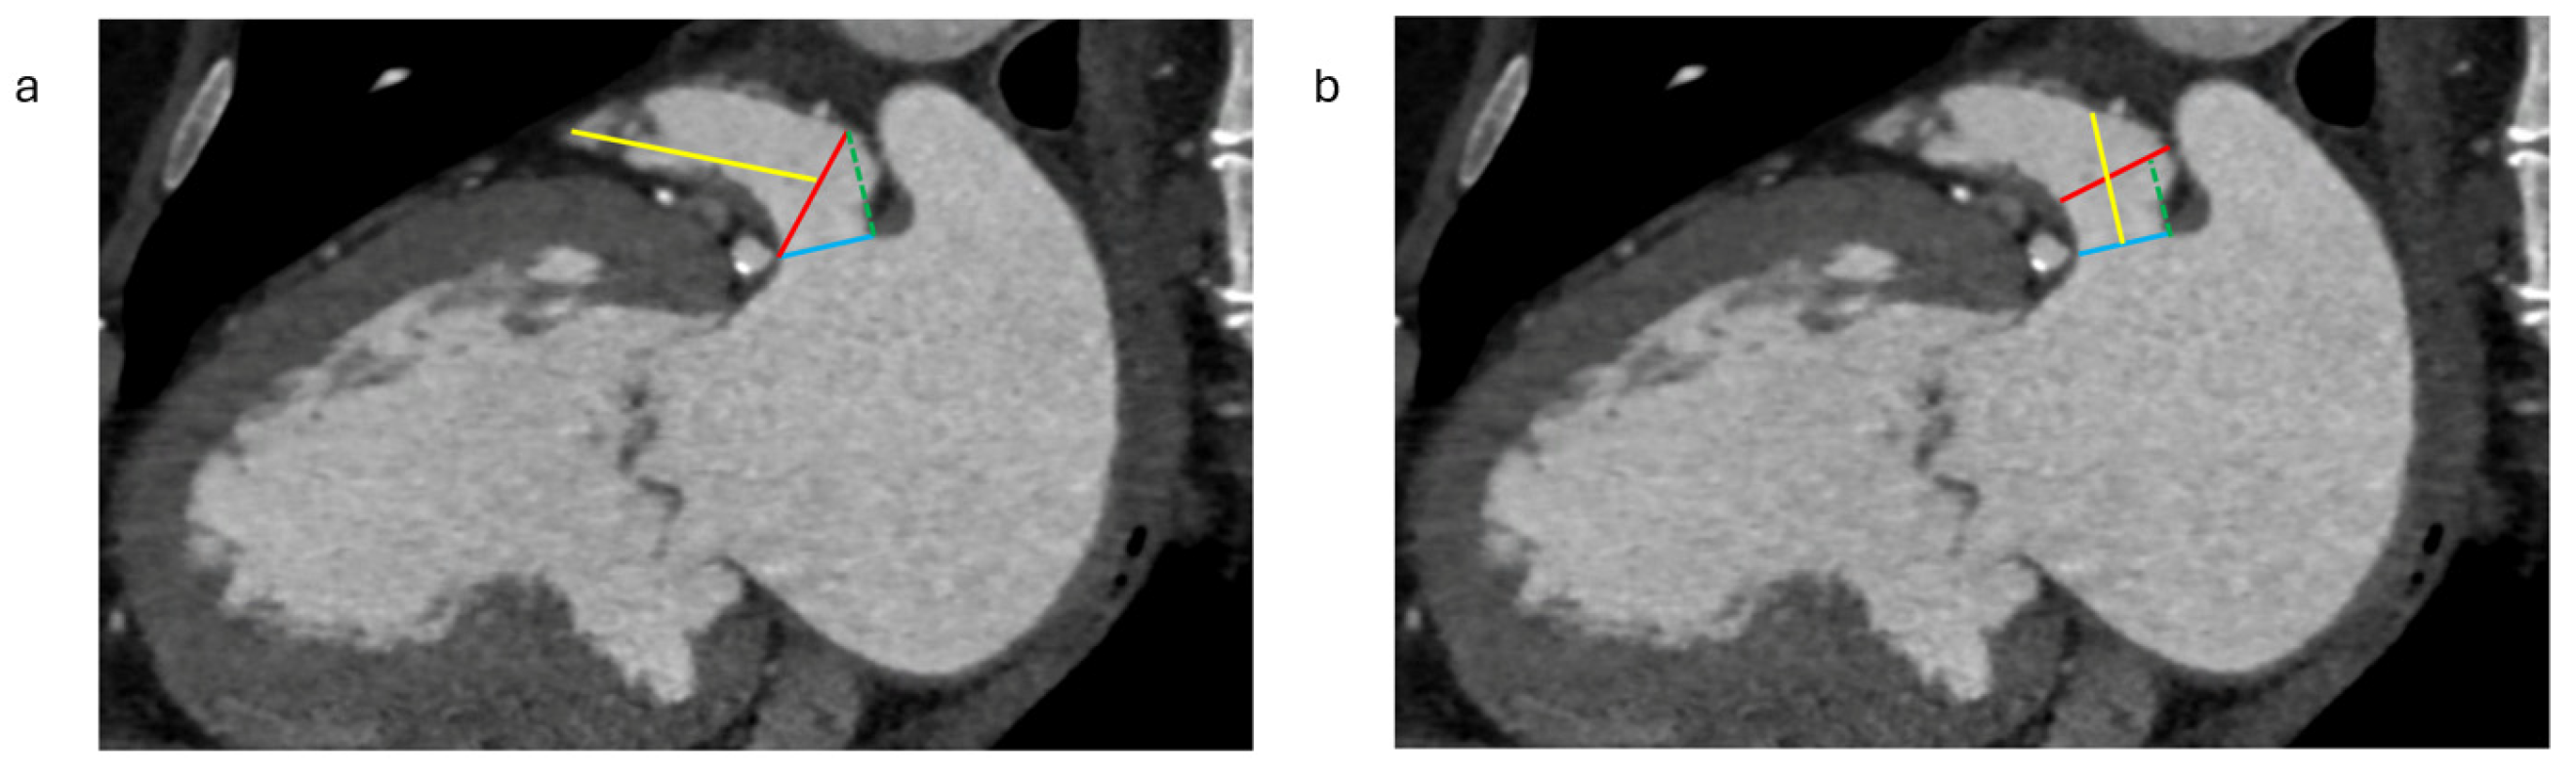

2.1.2. LAA Measurements

2.1.3. Assessment of the Inter-Atrial Septum